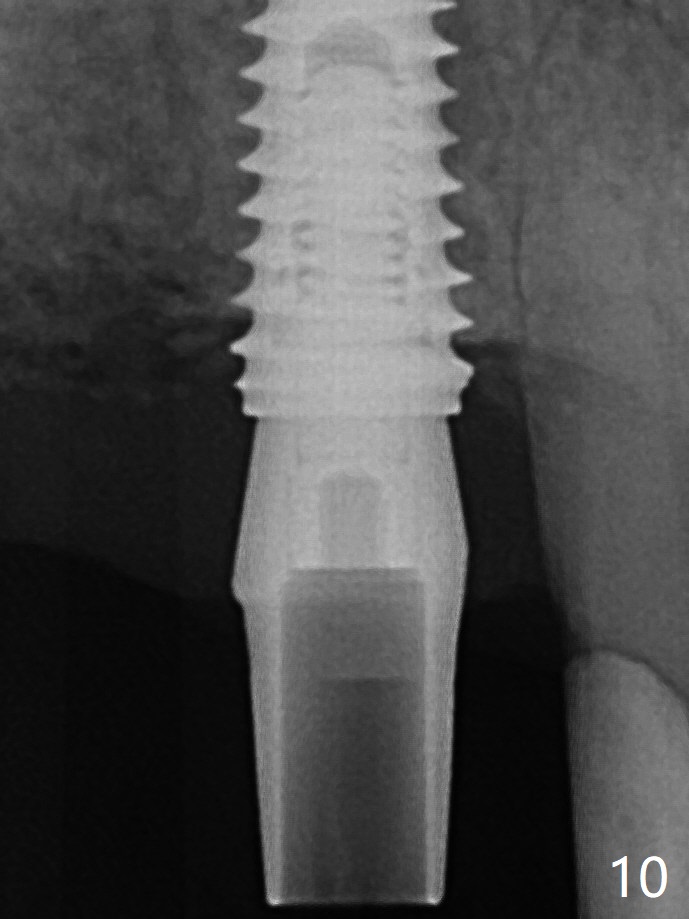

The incomplete abutment seating (Fig.5,7) is noted after retightening the loose cantilever FPD 1 year post cementation (Fig.9 <). After removal of the FPD, the abutment is reseated completely without interference of the proximal contacts (Fig.10).